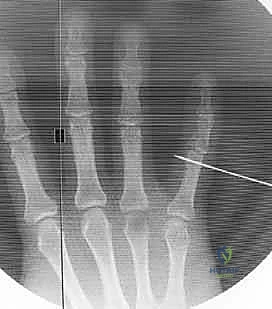

- Identify Distal Wire Level: Under image intensifier guidance, identify an appropriate level in the distal half to two-thirds of the middle phalanx. This placement must be distal to any fracture extension in the shaft of the middle phalanx to ensure adequate purchase in healthy bone. Mark this level on the skin.

> PEARL: For pilon fractures with significant distal extension, the distal wire can be placed as far distally as the head of the middle phalanx, or even near the center of rotation of the distal interphalangeal (DIP) joint. The middle phalanx is often narrowest proximally, so a more distal placement often provides a wider bone segment for easier and more secure wire placement. I have never encountered a fracture so distal that adequate fixation could not be achieved.

Figures 1D and 1E (TECH FIG 1D,E) illustrate finding and marking the position of the distal wire. Note how this placement is more distal than average, towards the head of the middle phalanx, due to an associated DIP joint injury, providing ample bone for fixation.

-

Initial Distal Wire Insertion: Similar to the proximal wire, insert the 1.1-mm K-wire percutaneously, aiming for the center of the middle phalanx. This wire must be perpendicular to the long axis of the finger and, crucially, parallel to both the plane of rotation of the PIP joint and the previously inserted proximal wire. This parallelism is essential for creating a functional dynamic construct.

Fluoroscopic Confirmation (Partial Insertion): Insert the wire partially through the middle phalanx and check its position carefully with both PA and lateral views on the image intensifier.

*Figures 1F and 1G (TECH FIG 1F,G) confirm the insertion and position of the distal wire on the image intens